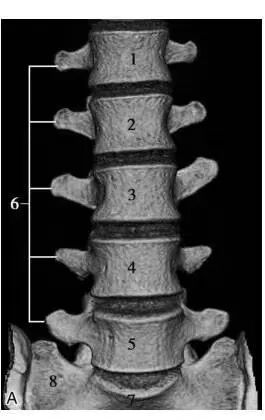

二、CT:也是利用x光扫描,可以围绕人体360度无死角的进行扫描。

(椎间盘突出,后纵韧带骨化)

优点:CT扫描能观察到横断面的细节,能了解腰椎的骨质情况、椎间盘突出和硬膜囊神经根的关系,椎间关节之间的情况等;可以做到薄层几百幅图像能更好的看清细小的病变,特别是微小的骨折;在扫描结束后可以通过影像后处理的方法,把腰椎图像重建成矢状位或冠状位,可从多个平面的不同角度去观察腰椎的影像情况。

缺点:辐射量相比DR成倍增加,而且还是不能很好的显示软组织结构、韧带及椎管内情况等。